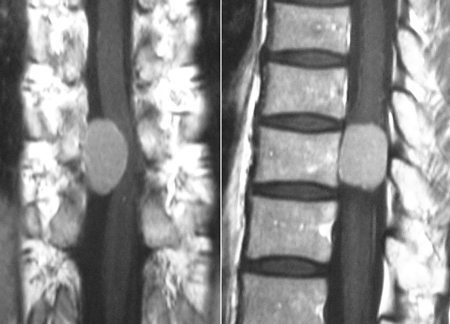

下のMRI画像は胸椎に発生した髄膜腫です.卵円形の腫瘍が造影剤により白く描出されています.左図が前後からみたところ,右図が横からみたところです.脊髄の前方に発生していない限り,比較的容易に摘出できます.